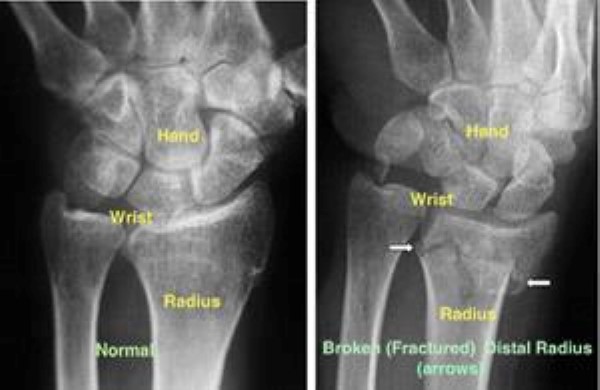

x-ray of distal radius fracture

(Left) An X-ray of a normal wrist. (Right) The white arrows point to a distal radius fracture.